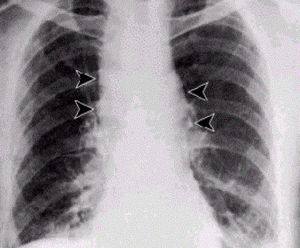

الأعراض والعلامات

إنَّ الأعراض الأولية للجمرة الخبيثة الاستنشاقية inhalation anthrax تكون خفيفة ولا نوعية وقد تشمل حمى ووعكة وسعال خفيف أو ألم بالصدر؛ وبعد 3-5 أيام تحدث أعراض حادة للضائقة التنفسية وظهور اتساع الـمَنْصِف في الصورة الشعاعية، ما في ذلك الاختناق ، ضيق التنفس الحاد ، hypoxemia ، diaphoresis وزرقة وصدمة ثم الوفاة بعد فترة قصيرة. والارتشاح البلورى شائع ، ويمكن أن ترى تسربات أحيانا على الصدر بالأشعة السينية. ويقدر الحد الأقصى لمعدل إماتة الحالات إلى اكثر من 85 ٪ ، والعلاج في وقت مبكر بمضادات الميكروبات العدوانية إلى جانب الرعاية الداعمة قد يقلل من نسبة الوفيات الكبيرة. الجمرة الخبيثة يمكن علاجها في المرحلة المبكرة ، ولكن الوفيات لا تزال مرتفعة على الرغم من المعالجة المضادة للجراثيم إذا كان بدأ العلاج بعد بداية الأعراض التنفسية. في البلدان التي تتوطن فيها الفقيرة ، وحيث قيمة اللحوم من الحيوانات التي قد ماتت بشكل غير متوقع تفوق المخاطر المتصورة من المرض التي قد تنجم عن تناوله . الجمرة الخبيثة الابتلاع ليست من غير المألوف ، ويمكن أن تتخذ شكل الجمرة الخبيثة في البلعوم الفمى، ولكنهاأكثر شيوعا كجمرة خبيثة في الجهاز الهضمي. في الاولى الآفة في تجويف الفم ، على مخاطية الشدق واللسان واللوزتين ، أو جدار البلعوم الخلفي.التهاب الحلق واعتلال العقد اللمفية الإقليمية في الرقبة ، مع وذمة واسعة النطاق قد تؤدي الى انسداد القصبة الهوائية ، هي السمات الغالبة في وقت مبكر. في حالة الجمرة الخبيثة في الجهاز الهضمي ، الآفة قد تكمن في أي نقطة على طول الأمعاء ميببة تقرح وذمي على نطاق واسع ، مما يؤدى إلى نزيف ، و ثقب ، واستسقاء واسع النطاق. ابتلاع الجمرة الخبيثة ليست مميتة دائما ، ولكن ، حتى مع العلاج الوفيات يمكن أن تكون عالية ، مع تطور تسمم الدم والصدمة والغيبوبة والموت. فترة الحضانة بشكل عام 3 -- 7 أيام.